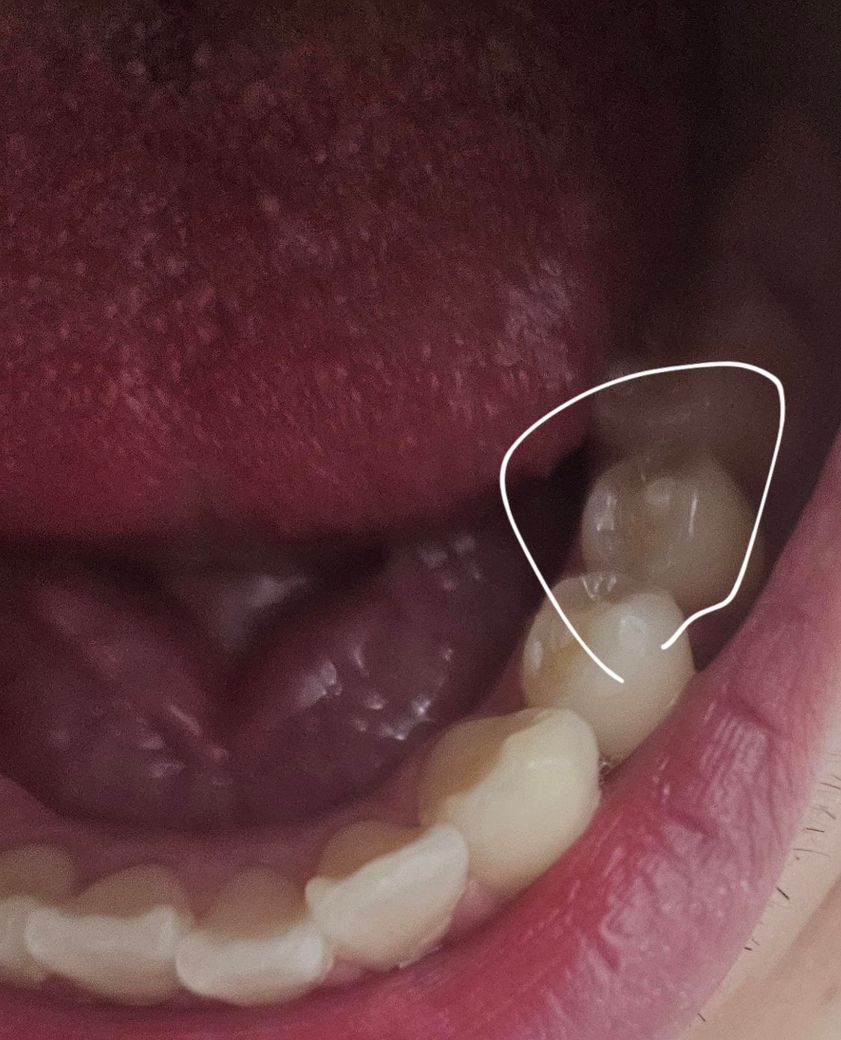

치과에서는 치외치에 원래 문제가 생겨야 알려주나여?

요즘 치아에 문제가 많아져서 1달만에 병원도 여러곳 가고 x-ray도 찍으면서 이리저리 여러 치과 병원을 다녀왔는데 오늘 처음으로 치외치라는 걸 알게 되었습니다. 이빨을 보니 파절된 치외치가 있는데도 뭔가 말해주는 치과가 없네여.. 원래 이가 문제 생겨야 말해주나여?

• 1번 째 사진

치외치의 경우에는 치위치가 있는 부위로 신경이 따라 올라와 있는 경우가 있기 때문에 해당 부위를 손을 대거나 하진 않습니다.

해당 부위가 파절이 되었을 경우 신경이 노출된다면 감염이 되어 극심한 통증이 있을 수 있습니다. 치위치가 있는 경우 치외치 부위가 파절되지 않도록 조심해서 치아를 사용하는 것이 좋습니다.

치외치가 있다는 것은 말씀드립니다만 해당 치아를 적극적으로 치료해야하는 지에 대해선 의견이 갈릴 수 있습니다.

치외치 자체가 크게 문제가 잇는건 아닙니다. 혹시 추후에 치외치가 깨지거나 그러면 시릴수 잇습니다. 치과에서 확인하면 관리 잘하시라고 일반적으로 설명은 해줍니다.

치외치는 파절 시 신경치료 가능성이 높기 때문에 발견되었다면 환자한테 치외치에 대해 설명해주고 특히 주의할 것을 고지합니다